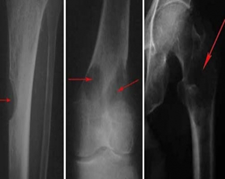

㈡骨痛、自發(fā)性骨折

骨髓瘤會造成人體骨骼的破壞增加,對胸腰椎、骨盆的破壞尤為明顯。這些負(fù)重骨骼,就像房屋的承重墻一樣,受損后就難以承受自身體重,容易發(fā)生骨折。即便沒有發(fā)生骨折,也常造成骨痛。查X片或CT發(fā)現(xiàn)多部位的骨質(zhì)破壞,也不能輕易漏過。